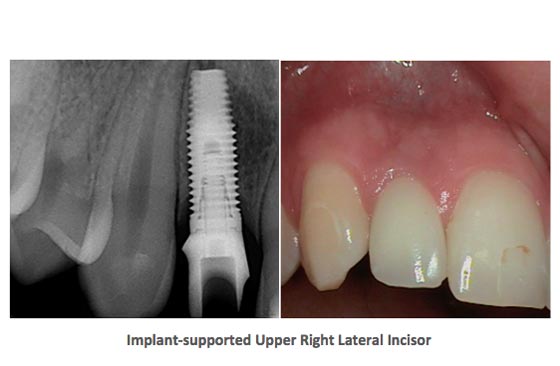

- Dental Implants